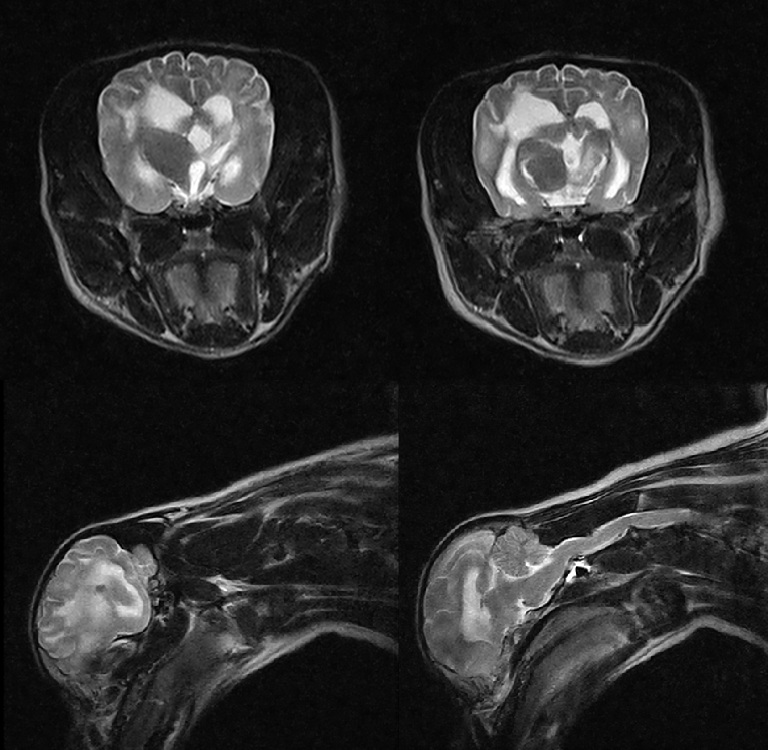

Високодеталізоване МРТ зображення нейрокраніуму собаки в поперечній проекції з чіткою візуалізацією структур мозку

Система забезпечує високу діагностичну ефективність при виявленні дегенеративних змін міжхребцевих дисків, пухлинних процесів та запальних захворювань центральної нервової системи